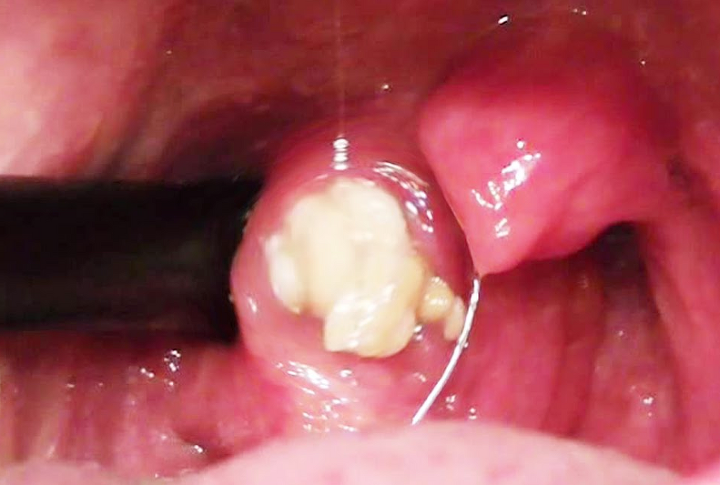

편도염, 후비루, 비염 등과 같은 염증이 생긴 이후 그 자리에 구멍이 생겨 점액, 타액, 음식물 찌꺼기가 그곳에 쌓여 생긴 것이 편도결석입니다.

온갖 찌거기가 쌓이다 보니 박테리아, 곰팡이 등이 생겨 악취가 나고 시간이 지나면서 단단해집니다. 사람에 따라 차이가 있지만 하나만 있을 수 있고 여러 개 가지고 있을 수 있습니다.

2. 편도결석 제거기

편도결석을 제거하기 위해 면봉을 사용하거나 손가락으로 자극하는 경우가 있습니다. 그러나 이는 염증을 유발해 더 많은 편도결석을 발생시킬 수 있습니다.

양치질을 하면서 편도선 주위를 압박(헛구역질)하여 제거할 수도 있으며 워터픽으로 입안을 헹구어 없앨 수 있습니다. 그러나 일반 워터픽을 사용할 때에는 수압이 세기 때문에 목안의 상처를 유발할 수 있으며 구멍이 터 커질 수 있어 조심해야 합니다.

이비인후과로 편도절제 수술도 한 방법이지만 집안에서 셀프로 제거할 수 있는 방법이 있습니다. 그것은 바로 편도결석 제거기를 사용하는 것입니다.